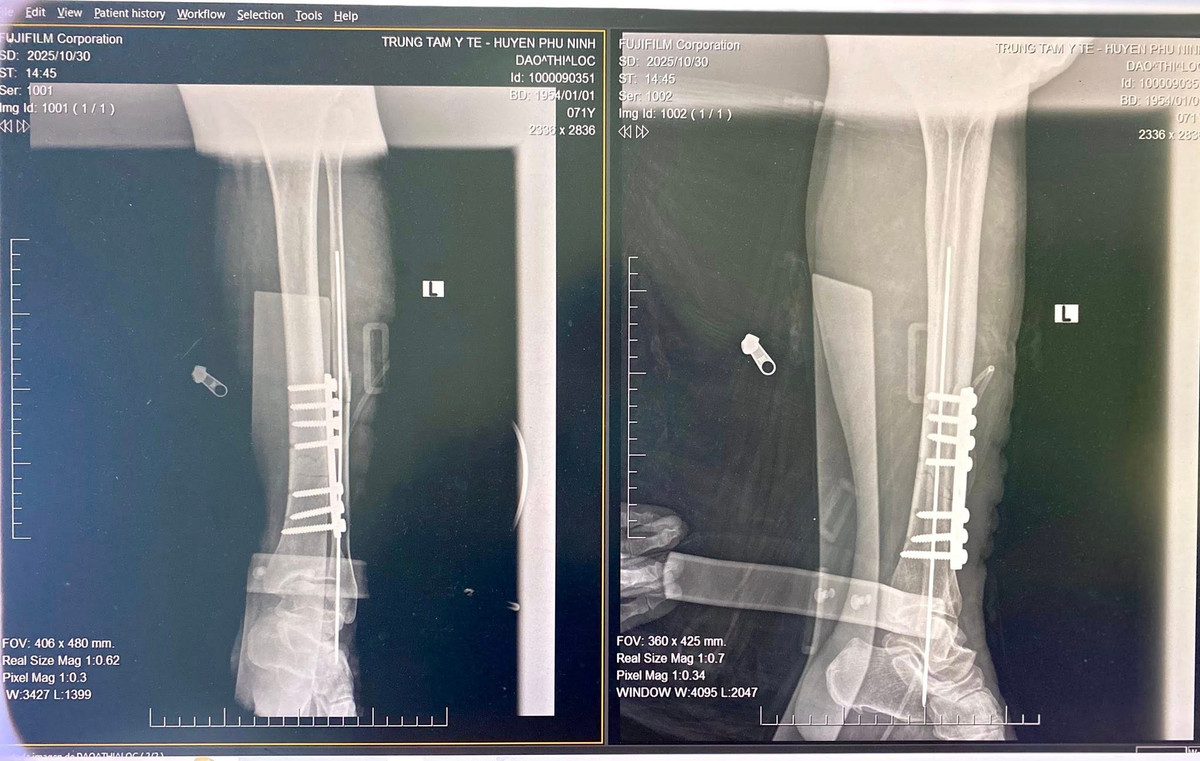

Sau 45 phút khẩn trương, ê-kíp phẫu thuật đã tiến hành ca mổ trong điều kiện vô khuẩn tuyệt đối. Với tay nghề vững vàng, thao tác chính xác và sự phối hợp nhịp nhàng, ca phẫu thuật diễn ra an toàn, thuận lợi. Hậu phẫu, người bệnh tỉnh táo, vết mổ khô, chi được cố định tốt, cảm giác và vận động dần hồi phục.

gay-xuong-3.jpg

Nẹp vít xương gãy sau phẫu thuật - Ảnh BVCC